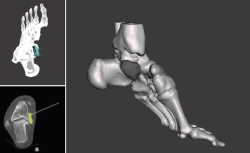

Figura 2. Modelo 3D del defecto del astrágalo.

Figura 3. Impresión de la guía 3D con el defecto del astrágalo y guía para su colocación.

- Obtención de la forma real del defecto combinando el astrágalo con una imagen especular del astrágalo contralateral (Figura 2).

- Impresión 3D del defecto del astrágalo y guía para la colocación de las agujas (Figura 3).